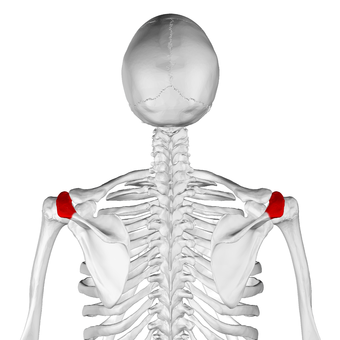

Acromion of left scapula01.png

عظم الكتف الأيسر. صورة أمامية. يظهر الأخرم باللون الأحمر.